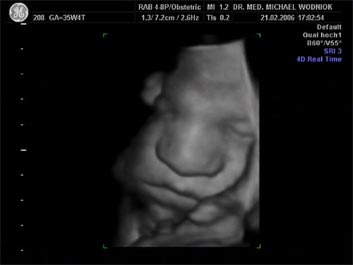

Weitere Ultraschalluntersuchungen sind in der 10./20./30. Schwangerschaftswoche gemäß den Mutterschaftsrichtlinien vorgesehen. Bei erkennbaren Risiken werden  weitere Untersuchungen angeschlossen. Spezielle Ultraschalluntersuchungen zum Ausschluss von kindlichen Entwicklungsstörungen sowie Durchblutungsmessungen der mütterlichen und kindlichen Blutgefäße mittels Farbdopplersonographie gehören zum Leistungsspektrum der Praxis. Auf Wunsch können auch 3D und 4D Untersuchungen angeboten werden.